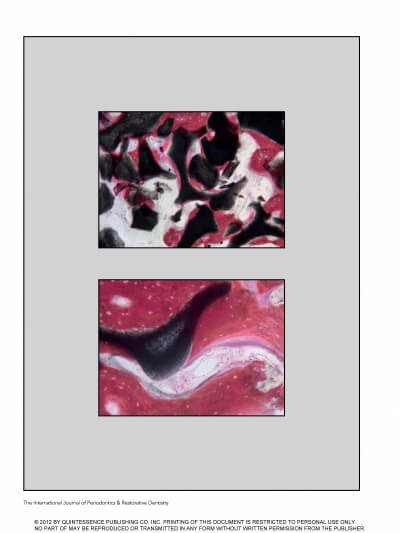

MAXILLARY SINUS AUGMENTATION- 3 CASES

SINUS FLOOR AUGMENTATION WITH HYDROPNEUMATIC TECHNIQUE

SINUS AUGMENTATION PROCEDURES